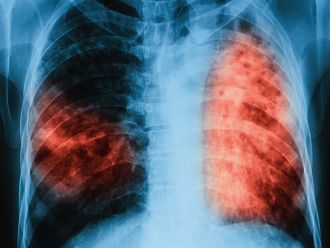

Медицинските консултации и изследванията са напълно безплатни, включително и за неосигурените лица. На всеки, който реши да провери своето състояние, ще бъде извършен преглед и ще се назначи проба манту, а при необходимост и допълнителни изследвания – рентгенова снимка и изследване на материал за туберкулозни бактерии.

По време на кампанията, организирана през месец септември т.г. в МБАЛ – Смолян, са преминали 128 човека. От тях с риск от заболяване са 118. На 103 човека са направени проби манту, на 41 рентгенография на бял дроб, на 12 микробиологично изследване на храчка. При 18 пациенти е открита латентна туберкулозна инфекция, 18 души са обхванати с химиопрофилактика. Няма открити болни от туберкулоза.